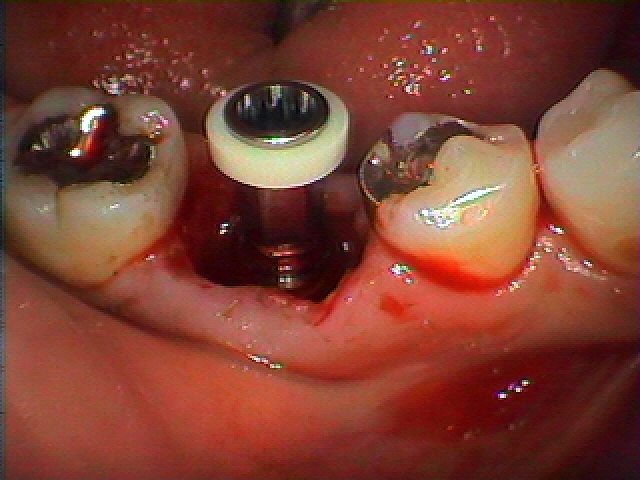

抜歯即時インプラント埋入となりました

大きく骨欠損は認められ、下顎管神経までそんなに余裕もない歯でした

このように埋入し、縫合して終了となります

隙間には骨補填材を填入しています

抜歯時になります

2か月待ち、インプラント部の上部構造を立てていきます